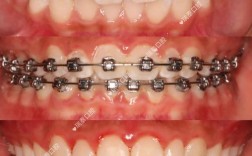

(二)咬合检查

- 覆合覆盖:正中颌位时,上颌中切牙切缘覆盖下颌中切牙唇面6mm(深覆盖Ⅲ°),上颌中切牙牙冠覆盖下颌中切牙牙冠2/3(深覆合Ⅱ°);

- 中线:上颌中线右偏2mm(与上颌中切牙旋转相关),下颌中线居中;

- 磨牙关系:右侧上颌第一磨牙近中尖对下颌第一磨牙近中颊尖(安氏Ⅰ类关系),左侧上颌第一磨牙近中尖对下颌第一磨牙颊沟(安氏Ⅰ类关系);